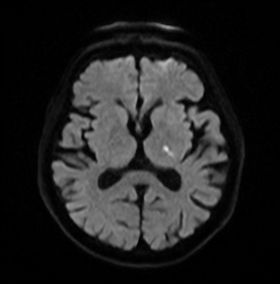

過去の小さな脳梗塞や出血の痕跡、自覚症状のない隠れ脳梗塞などもMRIで検出できます。これらは将来的な脳卒中のリスクを示す重要な情報です。 - 脳腫瘍の有無:

脳にできる良性・悪性の腫瘍も、MRIによって早期に発見できる可能性があります。 - 脳萎縮の程度:

加齢による脳の萎縮の程度を評価し、認知症のリスクなどを判断する手助けとなります。 - その他の脳疾患の早期発見: